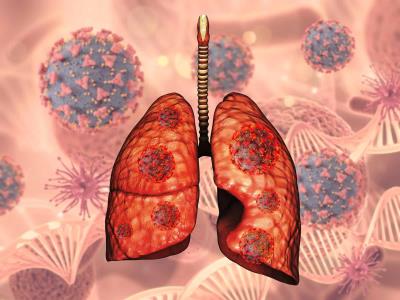

La información la compartió el viceministro de Salud Colectiva, Eladio Pérez, quien explicó que la tuberculosis es un problema de prioridad mundial para la Salud Pública, no sólo local, ya que es una enfermedad infecciosa y transmisible que afecta los pulmones y que preexiste en una infección oportunista presentada con frecuencia en personas con inmunodeficiencia, incrementando el riesgo de padecerla.